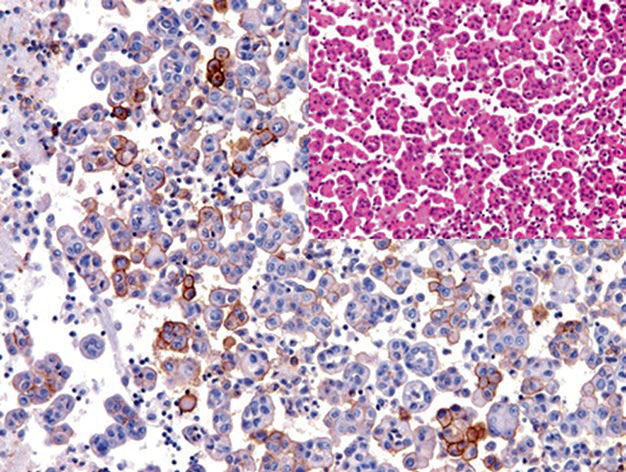

Figure 2. CD141 positivity in mesothelioma cells in malignant pleural effusion.

Positive expression pattern: Cell membrane